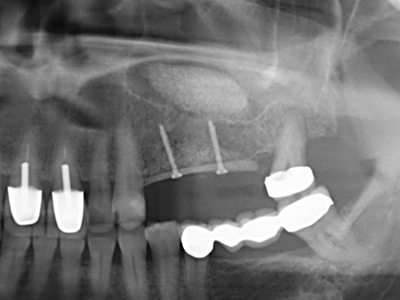

Bone tissue is not simply a mineral structure but also contains a substantial proportion of collagen fibres. This means it not only has good compressive strength but also a degree of flexibility, which can be taken advantage of when performing bone augmentations. In the classical expansion procedure using bone splitting, the atrophied alveolar ridge is split longitudinally and carefully expanded after reaching an adequate osteotomy depth (Fig. 13-16), ideally without substantial removal of the periosteum (Brugnami, Caiazzo et al. 2014, Stricker, Fleiner et al. 2014). Screw and plate systems with increasing expansion distance have proven effective in separating the two bone lamellae while remaining below the fracture threshold. In general, residual bone widths of at least 3–4 mm are required (Chiapasco, Zaniboni et al. 2006) to guarantee adequate flexibility and sufficient bone coverage of the future implants. If necessary, a vertical relief osteotomy on one or both sides can improve flexibility. A combination with additional augmentation techniques, particularly on the buccal side, has been described as an alternative to the classical technique.

The splitting procedure is particularly atraumatic and there is no significant loss of dimension when using piezosaws, and there are no significant differences between implants in split jaws and implants in an alveolar ridge without a bone deficit (Chiapasco, Zaniboni et al. 2006, Danza, Guidi et al. 2009). However, sufficient continuous irrigation is essential, particularly with locally restricted and deep splitting to prevent thermal stress in the apical osteotomy regions.